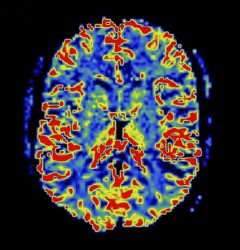

The hippocampus – a brain region involved in learning and memory – is abnormal in schizophrenia. Neuroimaging studies offer evidence of altered hippocampal activity, but mostly rely on a single hemodynamic parameter, for example blood volume or blood flow, and report mixed results.

Pratik Talati, a graduate student in Psychiatry, Swati Rane, Ph.D., research instructor at the Vanderbilt University Institute of Imaging Science, and colleagues used dynamic susceptibility contrast-MRI to simultaneously assess several hemodynamic measures – blood volume, blood flow and mean transit time (an indicator of circulation) – in the hippocampus of patients with chronic schizophrenia and healthy controls. They report in the June 30 issue of Psychiatry Research: Neuroimaging that patients with schizophrenia have significantly increased blood volume but normal blood flow and mean transit time in the hippocampus. The uncoupling of blood volume from flow could be due to antipsychotic medications or other factors, the authors suggest.

The findings support the use of multiple hemodynamic parameters to better link hippocampal function with clinical features of schizophrenia.